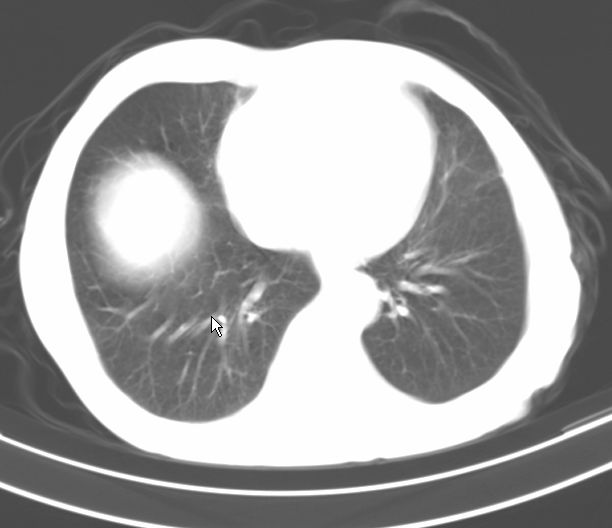

请大家看看是什么性质的。炎性病变首先考虑哪一种炎症。

支持右肺上叶前段\\下叶内基底段感染,建议抗炎治疗后复查,除外结核.

支持右肺上叶前段\\下叶上段感染,建议抗炎治疗后复查,除外结核.

支持右肺上叶前段、下叶内基底段感染,建议抗炎治疗后复查,除外结核.

右肺上叶前段及下叶内基底段感染性病变;建议抗炎治疗后复查。

楼主说是炎症,凭啥?典型的周围型肺癌(腺癌可能性大),肝内可能已有转移,强化看看吧。